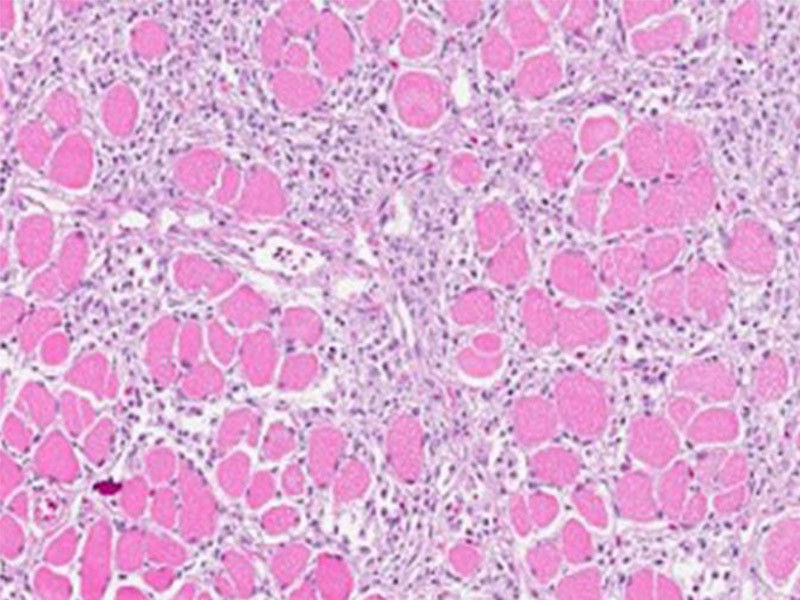

Laks fôret med en forbedret aminosyrediett under smitteforsøk med PD har bedre regenerering av muskel (mindre vevsskade) mot slutten av sykdomsforløpet.